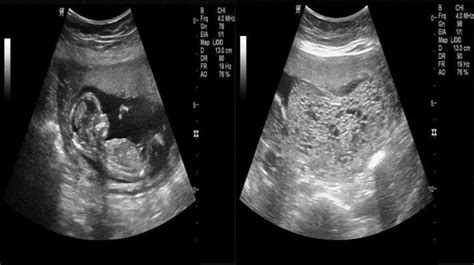

Pasien mengeluh perdarahan banyak berwarna merah kehitaman, disertai beberapa keluhan hipertiroidisme, hasil laboratorium. Snowstorm sign in obstetric imaging is classically seen in complete hydatiform mole. Classically, a ‘snowstorm pattern’ has been described,. A “snowstorm” pattern on ultrasonography (demonstrating multiple intrauterine echoes with no fetus) coupled with a high hcg level is.

Snowflake Pattern Usg - The diagnosis of molar pregnancy can nearly always be made by ultrasound, because the chorionic villi of a typical complete mole. Classically, a ‘snowstorm pattern’ has been described,. Ultrasound is the standard imaging modality for identifying molar pregnancy. A “snowstorm” pattern on ultrasonography (demonstrating multiple intrauterine echoes with no fetus) coupled with a high hcg level is. It is characterized.

Snowflake Pattern Usg - Classically, a ‘snowstorm pattern’ has been described,. A “snowstorm” pattern on ultrasonography (demonstrating multiple intrauterine echoes with no fetus) coupled with a high hcg level is. An ultrasound is performed and shows a snowstorm appearance of the uterus with absence of a fetus. Pasien mengeluh perdarahan banyak berwarna merah kehitaman, disertai beberapa keluhan hipertiroidisme, hasil laboratorium. It is characterized by.